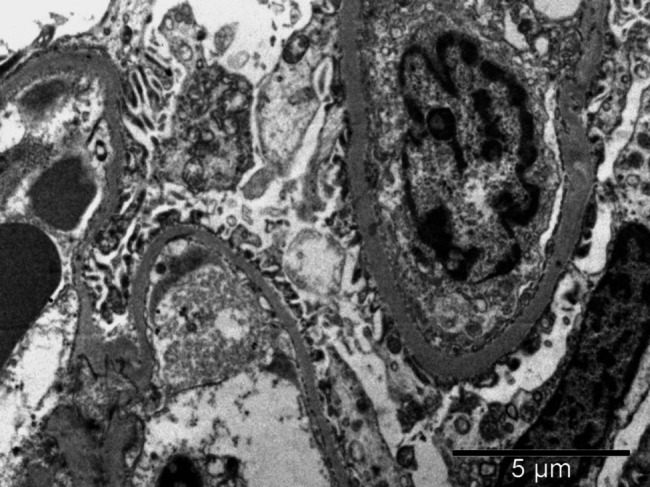

How does LAMB2 contribute to kidney disease? Insights from a pediatric case.